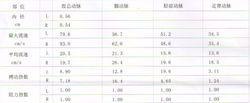

TCCD(1)收縮期峰值流速(Vs):指收縮期內的最高血流速度,也反映了整個心動周期內的最高血流速度;

(2)舒張末期血流速度(Vd):指心室舒張期末的最高血流速度,在一定程度上反映了腦血管的彈性與血管阻力;

(3)搏動指數(PI):是指評價動脈彈性和順應性的指標;

(4)阻力指數(RI):為反映血管舒縮情況,阻力狀況的指標;

(5)收縮/舒張流速比值(S/D):是評價腦血管順應性的一個指標。